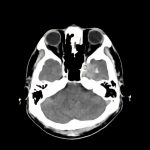

脳腫瘍

断層撮影

手術前1

No.’14_170 手術前1